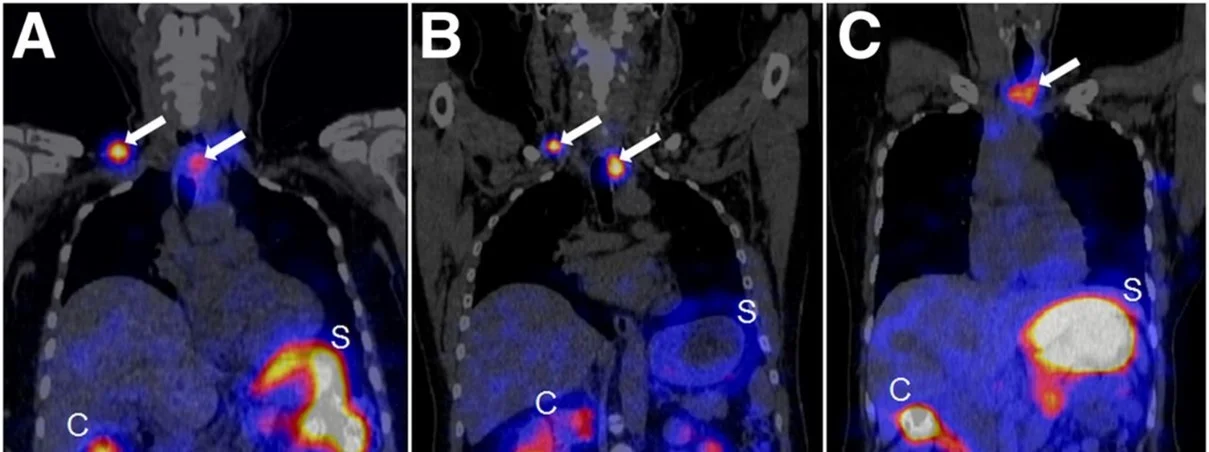

The treatment of patients with advanced medullary thyroid carcinoma (MTC) remains another significant clinical challenge. The cholecystokinin B receptor (CCKBR) has emerged as a promising target for MTC therapy using radiolabeled minigastrin analogs. However, kidney toxicity limits their therapeutic application. In the collaborative study with University Hospital Basel theragnostic suitability of developed by our group radiolabeled minigastrin analog [177Lu]Lu-PP-F11N was evaluated in MTC patients. The first clinical application of [177Lu]Lu-PP-F11N revealed efficient intratumor accumulation by single photon emission computed tomography (SPECT) in MTC patients [Sauter et al., 2018. J Nucl Med]. More recently, high tumor accumulation of metabolically stable radiolabeled minigastrin [177Lu]Lu-PP-F11N was demonstrated in MTC patients with low adverse reactions [Rottenburger et al., 2020. J Nucl Med] (Fig. 9).

Fig 9.

SPECT/CT scans 24 h after 177Lu-PP-F11N injection in MTC patients. (A-C) Tumors are indicated by arrows. Adapted from Rottenburger et al., 2020. J Nucl Med.

Importantly, the compound exhibited a favorable biodistribution profile with low radiation doses to the kidneys and bone marrow, although the stomach was identified as the dose-limiting organ. Currently, further clinical investigations of [¹⁷⁷Lu]-PP-F11N are underway, including combination with other treatment modalities, to improve tumor-specific uptake and therapeutic efficacy in MTC patients.